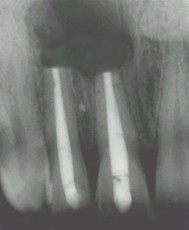

La résection apicale

Mais il est des cas où l'intervention chirurgicale s'impose pour mettre un terme à la lésion apicale. C'est ce que l'on appelle "la résection apicale", sous anesthésie locale.